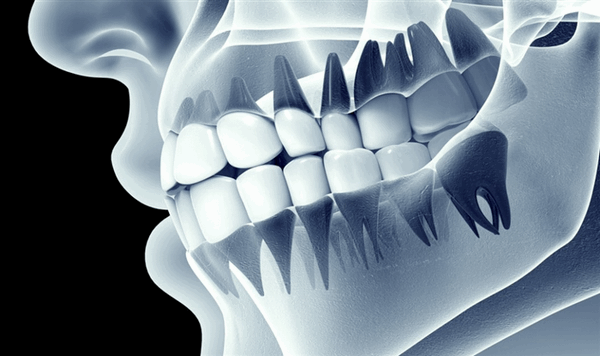

Проводится с целью выявить состояние костной ткани и зубных корней, исключить противопоказания. Если вы лечите один зуб, будет достаточно прицельного снимка (рентген). Если врачу необходимо увидеть картину целиком, нужен обзорный снимок (ортопантомограмма). Перед имплантацией вас направят на компьютерную томографию.

Панорамный снимок, КТ. Позволяют увидеть состояние челюстной системы, костной ткани, нервов, носовых пазух. На основании этого врач расписывает план лечения.

Рентгенография

Для определения состояния костной ткани проводится пальпация альвеолярных отростков и назначается рентгенографическое обследование (панорамный снимок, ОПТГ). Это позволяет оценить высоту кости и расположение зубов, однако у ОПТГ есть искажения размеров до 20%. Поэтому дополнительно могут назначить компьютерную томографию (КТ) для получения трехмерного изображения строения челюсти.

- Ширина костной ткани в щечно-язычном отделе должна быть от 6 мм.

- Расстояние между зубными корнями не менее 8 мм.

- Оптимальная толщина кости на верхней/нижней челюсти 10 мм (в других случаях понадобиться оперативная подготовка).

Диагностика состояния костной ткани

Чтобы провести диагностику состояния челюсти, врач делает панорамный снимок (ортопантомограмму). На рентгеновском снимке ОПТГ можно увидеть расположение корней зубов, наличие гранулемы, кисты, проседание кости (уровень резорбции), высоту костной ткани. Перед установкой протеза это не менее важные показатели, как и диагностика кариеса, так как по состоянию кости можно определить, какой вид протеза можно установить. Наличие атрофии кости является противопоказанием к установке некоторых видов протезов.